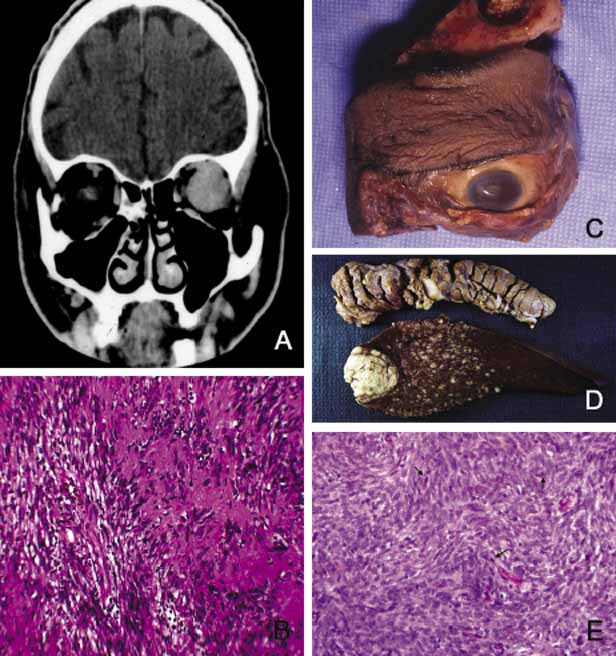

Cavernous hemangioma is another benign vascular tumor that occurs in adults, usually as a solitary, unilateral lesion, but multiple tumors have been described.185,186 Unlike capillary hemangioma it is not associated with other lesions elsewhere in the body. It is usually located within the muscle cone but may also be seen in extraconal locations and presents with slowly progressive proptosis without too much extraocular motility disturbance (Fig. 18). Gross appearance of cavernous hemangioma is a well encapsulated reddish purple lesion with a sponge-like consistency on its cut surface. Histopathologically, it consists of dilated vascular channels lined by endothelium and smooth muscle and intervening fibrous stroma. The endothelial cells are held together by tight junctions and display basement membrane reduction. Clinical differential diagnosis of cavernous hemangioma on imaging include fibrous histiocytoma, hemangiopericytoma, schwannoma and metastatic tumors.187 Surgical removal of the tumor is the treatment of choice.

Fig. 18 Cavernous hemangioma. Despite the presence of a large intraconal tumor in T1-weighted axial MRI, the left globe shows minimal proptosis because of the slowly growing nature of the tumor. This tumor was compressing onto the optic nerve to cause significant papilledema but the patient did not have any extraocular motility disturbance. The gross photograph of the transverse section of the well encapsulated cavernous hemangioma shows multiple loculations of the tumor. Histopathologically the Masson trichome stain demonstrates numerous caverns surrounded by thin fibrous septal, containing clusters of red blood cells. The arrow points to the capsule of the neoplasm. Note that some of the orbital fat is in fact within the fibrous tissues of the tumor (arrowheads).

Another lesion of this category that presents with large cavern formations surrounded by different amounts of fibrous tissue is lymphangioma.188–190 Unlike cavernous hemangioma, however, the space formations in this lesion are not lined by endothelial cells and do not contain vascular smooth muscle; the spaces are lined by flat mesothelial-like cells (Fig. 19). Spontaneous bleeding may take place within these cystic spaces resulting in “chocolate” cysts. In one-third of the cases, lymphoid follicles with germinal centers may be present in the intervening fibrous stroma and some tumors with abundant lymphoid tissue may respond to systemic steroid treatment. Because of the infiltrating nature of this tumor, surgery is not an early option of management; these lesions should be managed conservatively.190

Fig. 19 Lymphangioma. A 23-year-old woman with marked axial proptosis of the left eye secondary to lymphangioma (A). The tumor is depicted in the T1-weighted axial MRI showing a multiloculated tumor with marked enhancement occupying the entire orbit (B). Frame C shows multiple irregular lymphatic spaces (ls) that were changing in size and shape during the B-scan ultrasonography. The histopathology of the same case (D, E) reveals multiple lymphatic spaces (ls) lined by flat mesothelial-like cells surrounded with irregular fibroconnective tissue and lymphoid follicles with germinal centers (g). Note that some of the lymphatic spaces are filled totally or partially with blood.

Orbital varix is another orbital vascular lesion that develops as a distention of a venous channel leading to stagnant blood flow resulting in thrombus formation.191 Orbital varices are divided into primary lesions, confined to the orbit and secondary lesions associated with intraorbital and intracranial arteriovenous malformations.54 Vascular hamartomatous lesions may contain arteriovenous malformations with or without abnormal communication between arterial and venous vasculature. These lesions should not be confused with carotid cavernous and dural cavernous fistulas, which affect the orbit secondarily.192 If one clinically suspects an A-V malformation component in an orbital vascular lesion, CT angiogram and arterial and venous angiograms should be used to rule out the connection of the lesion to systemic circulation.193 Color Doppler flow imaging has also been used to examine these tumors. In addition to the above detailed vascular tumors, angiosarcoma, Kaposi sarcoma, intravascular papillary endothelial hyperplasia (IPEH), vascular leiomyoma and angiolymphoid hyperplasia with eosinophilia (Kimura disease), can rarely be encountered in the orbit.194–198

In this chapter, neural neoplasms are covered under two major groups: tumors originating from central nervous system (CNS) tissues, and tumors originating from peripheral nerves.

The two most commonly encountered tumors of the optic nerve that involve the orbit are optic nerve glioma and optic nerve meningioma.200

Optic nerve glioma (ONG) is primarily a tumor of childhood.201,202 When it presents in adults a more malignant glioma should be suspected.203 ONG is associated with neurofibromatosis type I (NF-I) with one or both optic nerves involved in approximately 25% of the cases.204 Some authors suggest that patients with NF-I may have a favorable prognosis. In general, the more anterior the glioma, the more favorable the prognosis.205